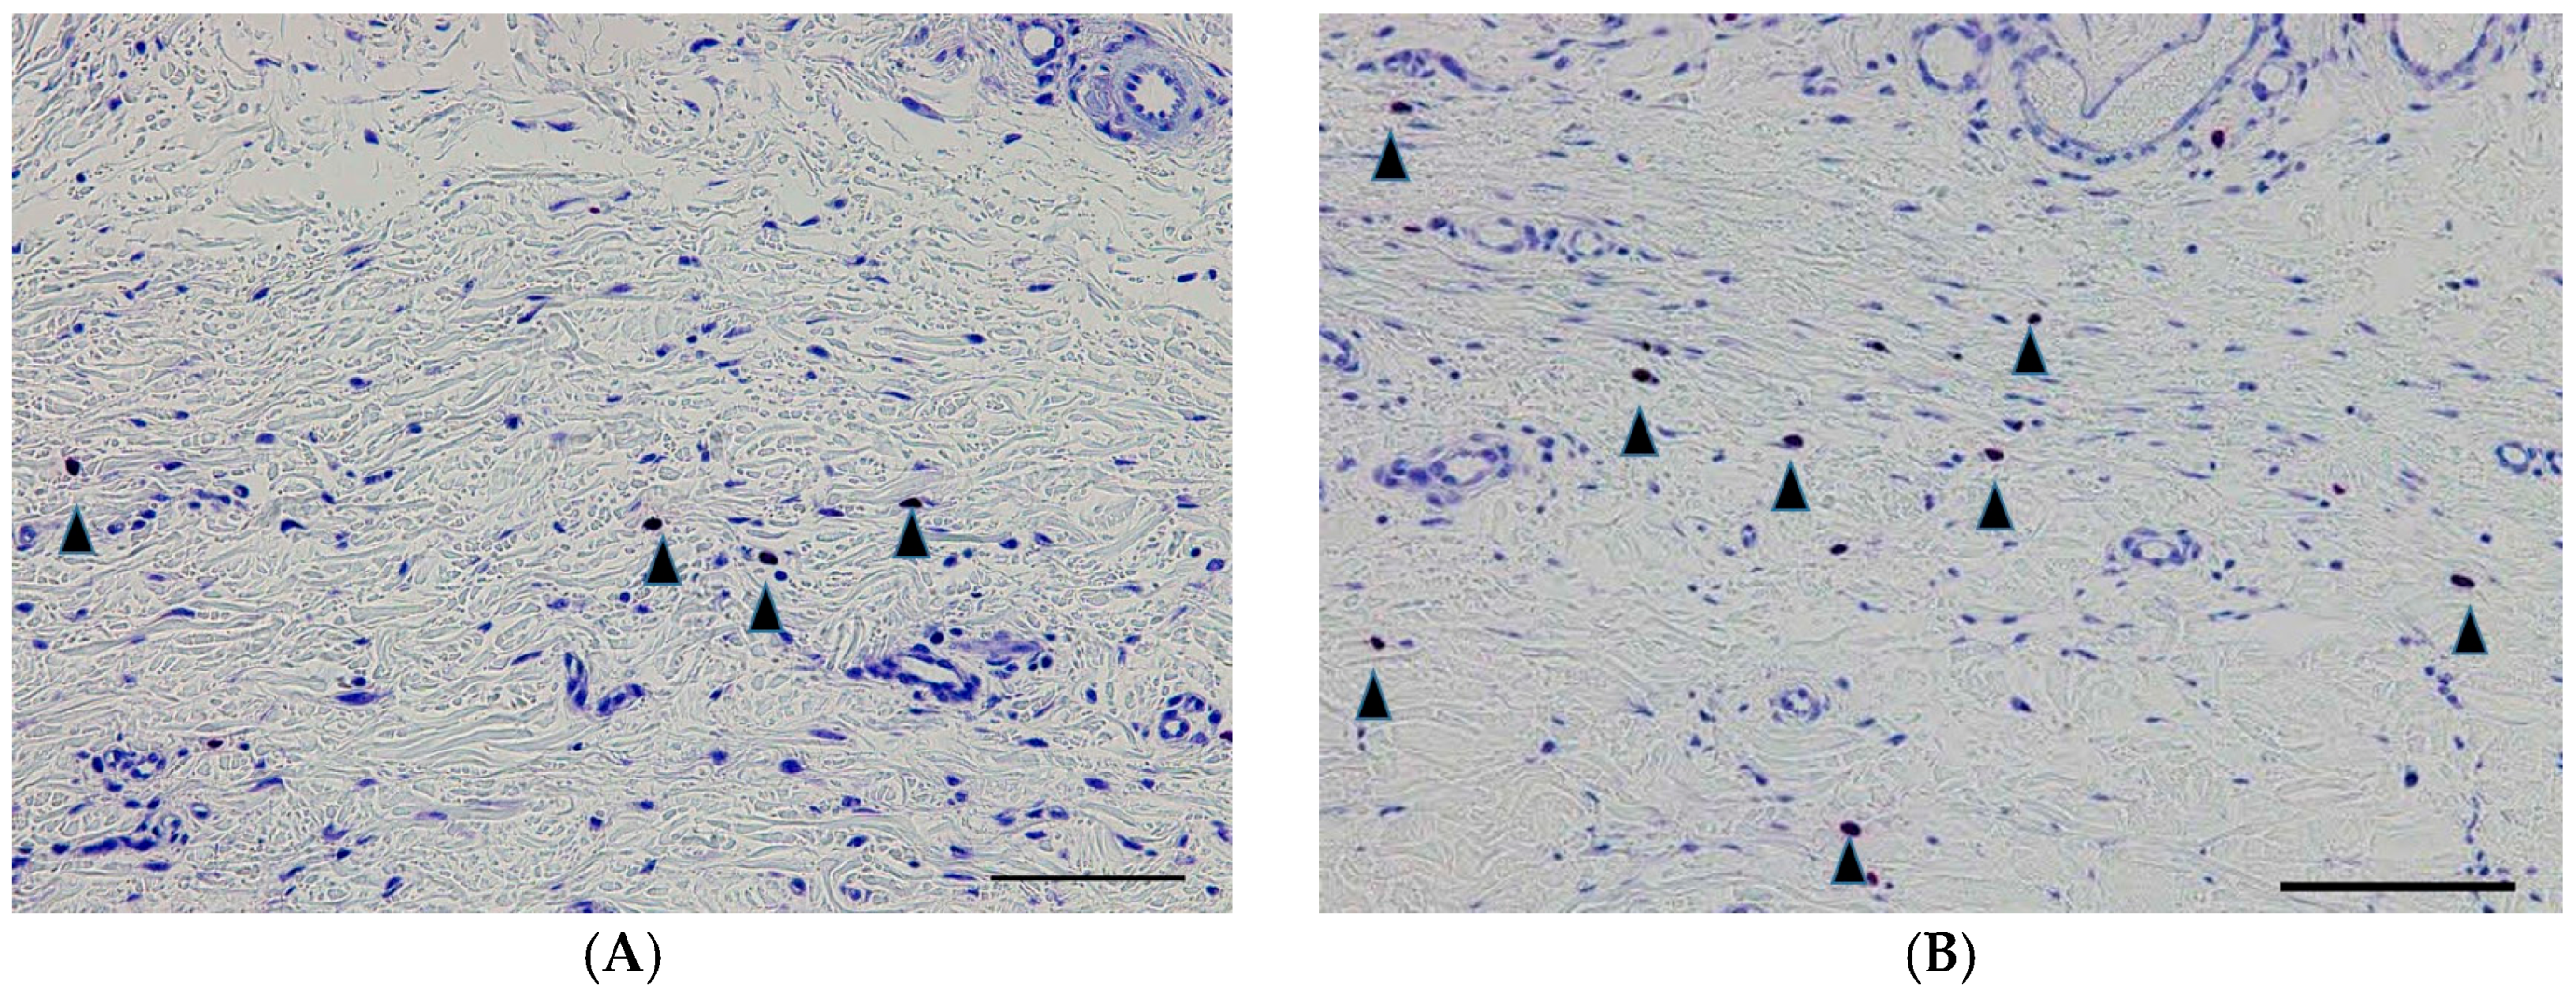

2.5. Vimentin-Positive Cells

| Density of fibroblasts, per mm2 | 27.8 ± 8.6 | 67.6 ± 18.7 | 0.01 |